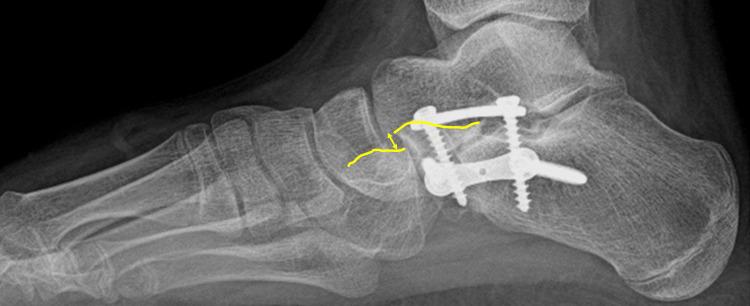

A case-control retrospective study was conducted on 50 patients (80 feet) aged 12.4±2.5 years who underwent CLP. A clinical (demographic parameters, etiology, Gross Motor Function Classification System (GMFCS) level) and radiological evaluation were assessed preoperatively and repeated postoperatively at 56.5±32.5 months. Two methods of osteotomy bone fixation were studied: K-wires vs. eight-plate. Standing anteroposterior (AP) and lateral (L) radiographs were done, and the following radiographic parameters were measured: calcaneocuboid (CC) joint subluxation classified into normal, moderate, and severe (L); AP and L talo-first metatarsal (T1MT) angle; AP talonavicular (TN) coverage angle; AP and L talocalcaneal (TC) angle; calcaneal pitch (CP) angle; and L talo-horizontal (TH) angle. Mosca's criteria were used for clinical and radiological assessments. The association between demographic data, clinical and radiological results, and the variation between preoperative and postoperative angles were studied. The main risk factors affecting clinical results and CC joint subluxation were investigated (logistic regression and analysis of covariance (ANCOVA)).

对50例(80足)年龄在12.4±2.5岁接受CLP手术的患者进行病例对照回顾性研究。术前进行临床(人口统计学参数、病因、粗大运动功能分类系统(GMFCS)水平)和影像学评估,并在术后56.5±32.5个月重复评估。研究了两种截骨内固定方法:克氏针与八孔钢板。拍摄站立位前后位(AP)和侧位(L)X线片,并测量以下影像学参数:跟骰(CC)关节半脱位分为正常、中度和重度(L);AP和L位距骨-第一跖骨(T1MT)角;AP位距舟(TN)覆盖角;AP和L位距跟(TC)角;跟骨倾斜(CP)角;以及L位距骨-水平(TH)角。采用Mosca标准进行临床和影像学评估。研究了人口统计学数据、临床和影像学结果之间的关联,以及术前和术后角度的变化。调查了影响临床结果和CC关节半脱位的主要危险因素(逻辑回归和协方差分析(ANCOVA))。